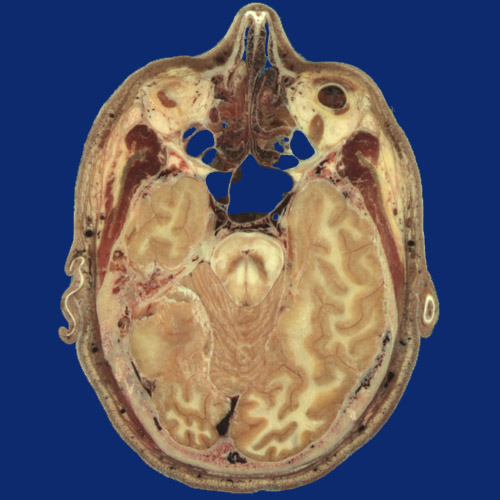

Identify the following regions in the image above: Nasal cartilage - Superior nasal concha - Nasolacrimal duct - Orbital fat pad - Inferior rectus - Inferior oblique - Maxillary sinus - Sphenoid sinus - Greater wing of sphenoid - Frontal process of zygomatic bone - Temporalis - Superficial temporal artery & vein - Clivus - Brainstem - Cerebral aqueduct - Cerebellum - Temporal lobe - Petrous part of temporal bone - Occipital vein - Occipitalis - Occipital lobe - Confluence of dural venous sinuses - Internal occipital protuberance